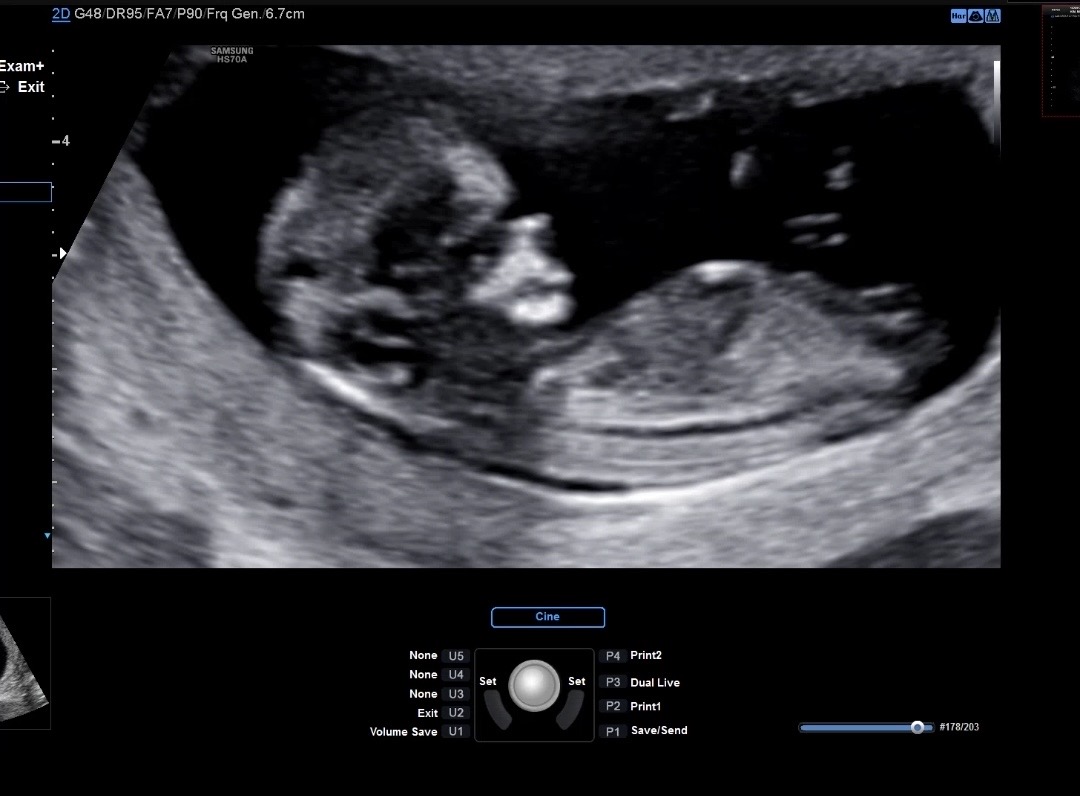

12주 2일 성별 참견 해주세요!!

아들일까요?? 딸일까요?? 첫 애기라 너무 궁금해서 여쭤봅니다 ㅎㅎㅎ 참견 부탁드리고, 참견 감사합니다😊 좋은 하루 보내세요🍀